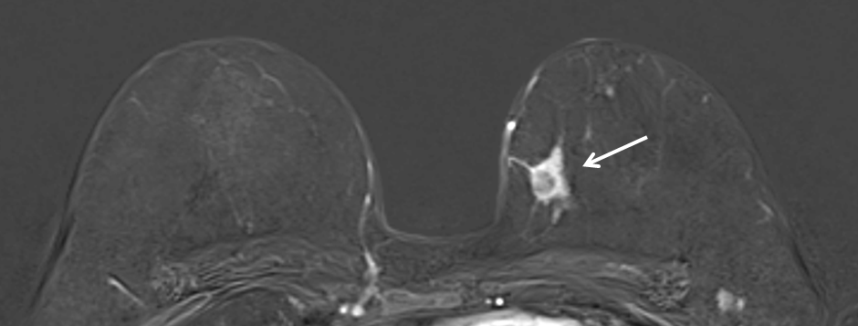

Kernspinuntersuchung einer 55jährigen Patientin mit gesichertem Karzinom in der linken Brust (im Bild rechts, Pfeil)

Bei der Kernspintomographie (= Magnetresonanztomographie oder MRT) der Brust werden mit Hilfe eines starken Magnetfeldes Schnittbilder beider Brüste erstellt. Die Untersuchung erfolgt ohne Röntgenstrahlen. Eine Kontrastmittelgabe ist in der Regel erforderlich. Die Kernspintomographie ist eine ergänzende Untersuchung, die bei speziellen Fragestellungen zusätzlich zu Sonographie und Mammographie durchgeführt wird. Bei Patientinnen mit Brustkrebs liefert sie oftmals wertvolle Zusatzinformationen zur Operationsplanung. Weiterhin findet sie bei speziellen Risikogruppen Anwendung, wie zum Beispiel bei Frauen, die bereits einmal wegen Brustkrebs operiert wurden oder Frauen mit nachgewiesen erhöhtem Brustkrebsrisiko, z.B. durch eine bekannte vorliegende Genmutation.

Die Kernspinuntersuchung der Brust ist nicht generell für die alleinige Brustkrebsfrüherkennung geeignet und kann auch nicht die Mammographie oder die Sonographie ersetzen.